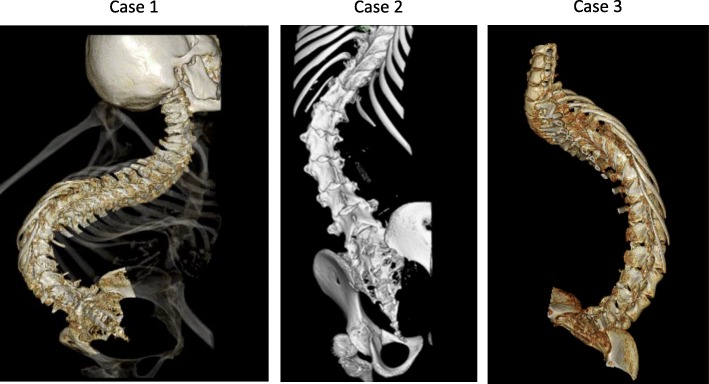

Fig. 1.

Reconstructed three-dimensional CT images of three cases. The volume-rendering reconstructions show marked scoliosis

Three-dimensional computed tomography (3D-CT) demonstrated that lumbar puncture at the L4/5 and L5/S1 interspace was possible in the prone position (Fig. 1). After a simulation in the interventional radiology suit, the patient was placed in the prone position with the right side slightly elevated on a surgical table, which was adjusted in a 30-degree reverse Trendelenburg position, and the left side was tilted at 45° in order to insert the needle (TOP spinal needle 25 G × 89 mm Quincke, TOP corp., Tokyo, Japan) vertically downward to the intrathecal space in a hybrid operating room.

Patient 2 was a 10-year-old girl (135 cm, 18 kg) with a diagnosis of SMA type 1 at the age of 6 months. Tracheostomy was performed when she was 4 years old. ADLs were performed with total assistance; muscle atrophy was significant; and joint contracture was observed. The patient had high-grade scoliosis, making it difficult to select a position. Three-Dimensional CT demonstrated that lumbar puncture at the L4/5 interspace was possible in the lateral decubitus position (Fig. 1).

Patient 3 was a 17-year-old girl (139 cm, 22 kg) with a diagnosis of SMA type 1 at the age of 11 months. Three-dimensional CT demonstrated that the lumbar spine was markedly rotated, and performing puncture was expected to be difficult (Fig. 1). Images obtained before the procedure confirmed that the dural sac terminated at the L5 level (Fig. 2); therefore, the needle (25 G × 70 mm) was inserted into the L3/4 (depth 45 mm), and nusinersen 12 mg (5 mL) was administered intrathecally after collection of 5 mL of CSF. There were improvements in motor function of extremities after second administration in all cases.

Nusinersen must be administered intrathecally, and lumbar punctures are often technically challenging because patients with SMA have spinal deformity and scoliosis, and spine rotation occurs during growth. Many techniques have employed the use of fluoroscopy, ultrasound, and cone-beam CT for successful intrathecal puncture [6–8]. Before the initial procedure in each patient, we assessed the position of laminar spaces on 3D-CT and determined the site and angle of the punctures. If the positioning of the patient at the time of puncture is expected to be difficult, we check the position in which the puncture can be performed by fluoroscopy in advance. The actual procedure is performed in a hybrid operating room where high-definition radiographs and c-arm CT images can be obtained. Other advantages of performing this procedure in an operating room include the ability to prevent infection and to ensure safety when difficulty with airway management or sudden changes associated with procedures and sedation occur.